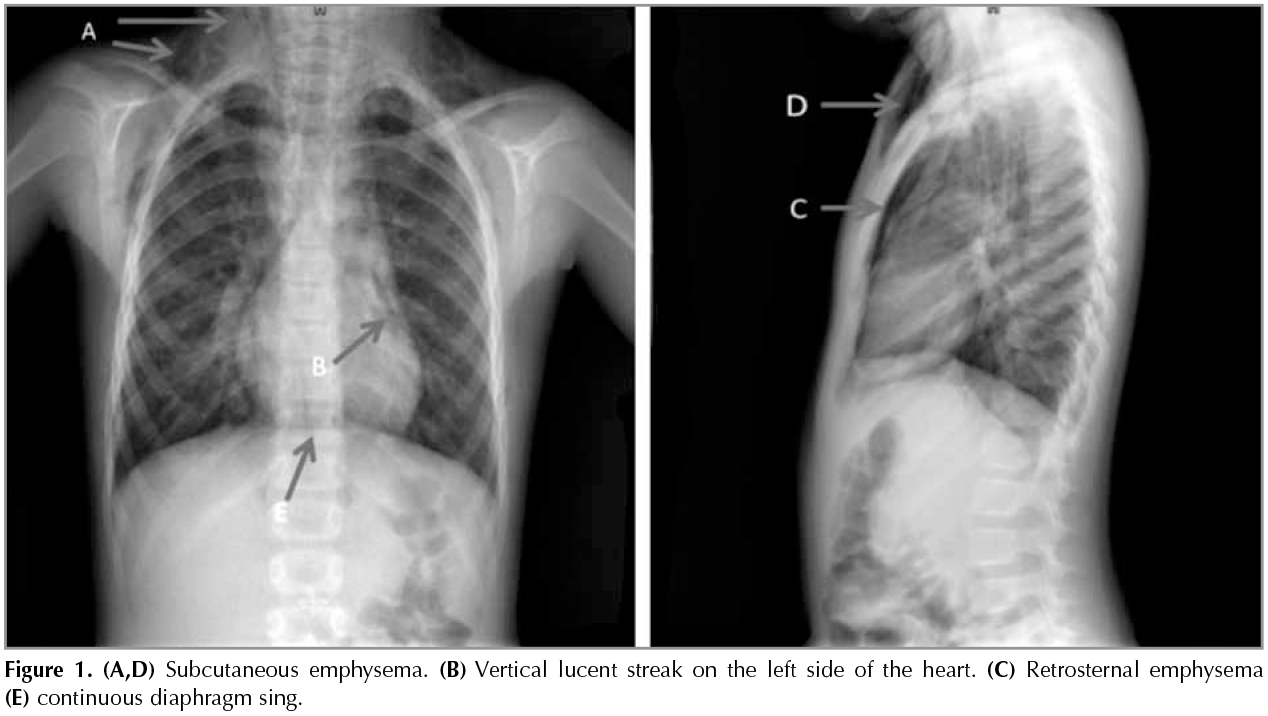

The chest X-Ray confirmed that she had subcutaneous emphysema on both sides of her neck, retrosternal emphysema, vertical lucent streak on the left side of the heart and continuous diaphragm sign.? No evidence was found of rib fracture or any abnormality within the lungs (Figure 1). White blood cell was 9430/mm3 and CRP was 1.6 mg/dL. Other laboratory findings including electrolyte levels, blood gas analysis were within normal limits. She was treated conservatively, and symptoms resolved 7 days postadmission.

Figure 1